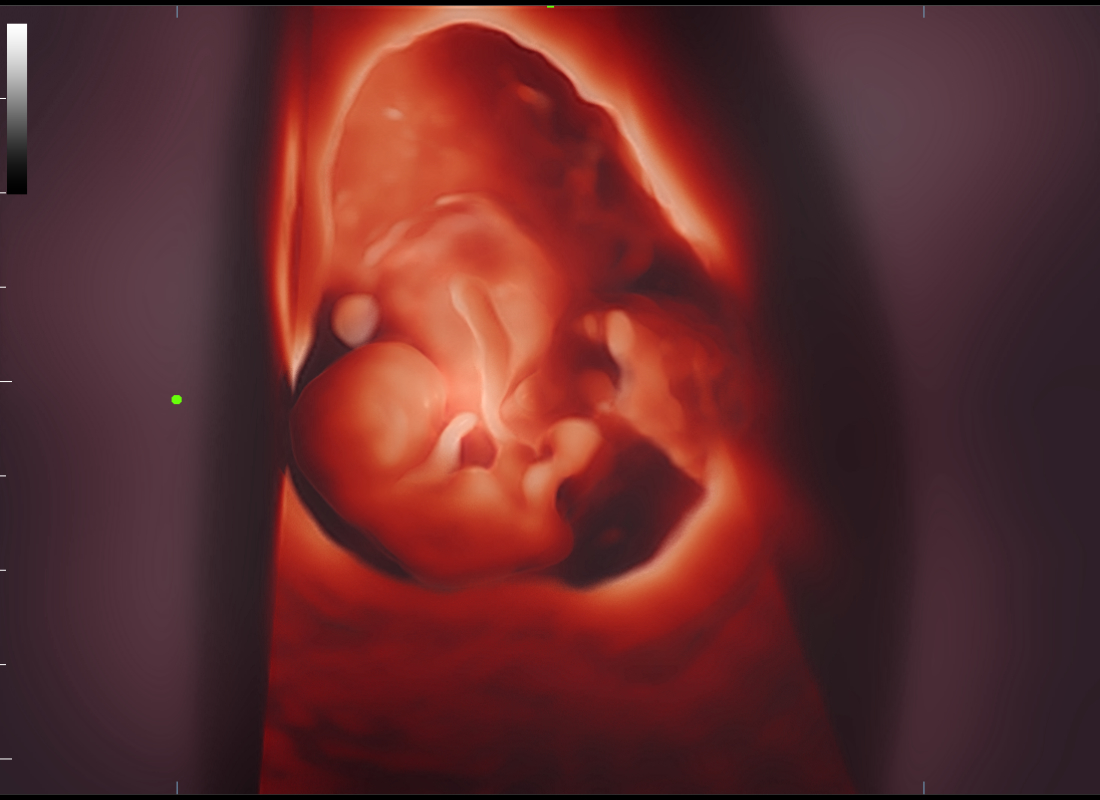

The volume imaging of fetal face is very important for the obstetric doctors whehere they make the face malformation diagnosis or a fully communication with parents. We deeply understand how Nuewa users need more intuitive fetal stereoscopic imaging to help parents quickly establish parent-child links at different gestational weeks.